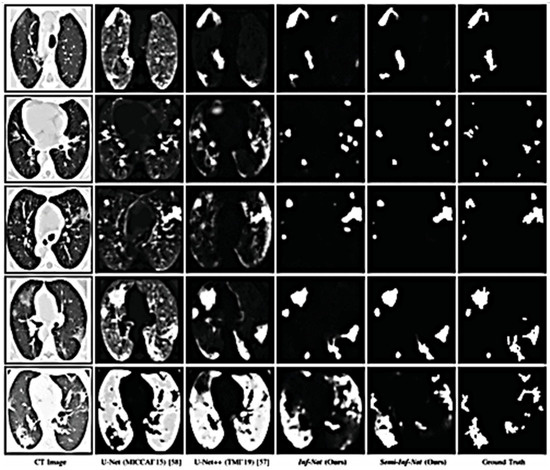

- Fan, D.P.; Zhou, T.; Ji, G.P.; Zhou, Y.; Chen, G.; Fu, H.; Shen, J.; Shao, L. Inf-net: Automatic COVID-19 lung infection segmentation from ct images. IEEE Trans. Med. Imaging 2020, 39, 2626–2637. [Google Scholar] [CrossRef] [PubMed]